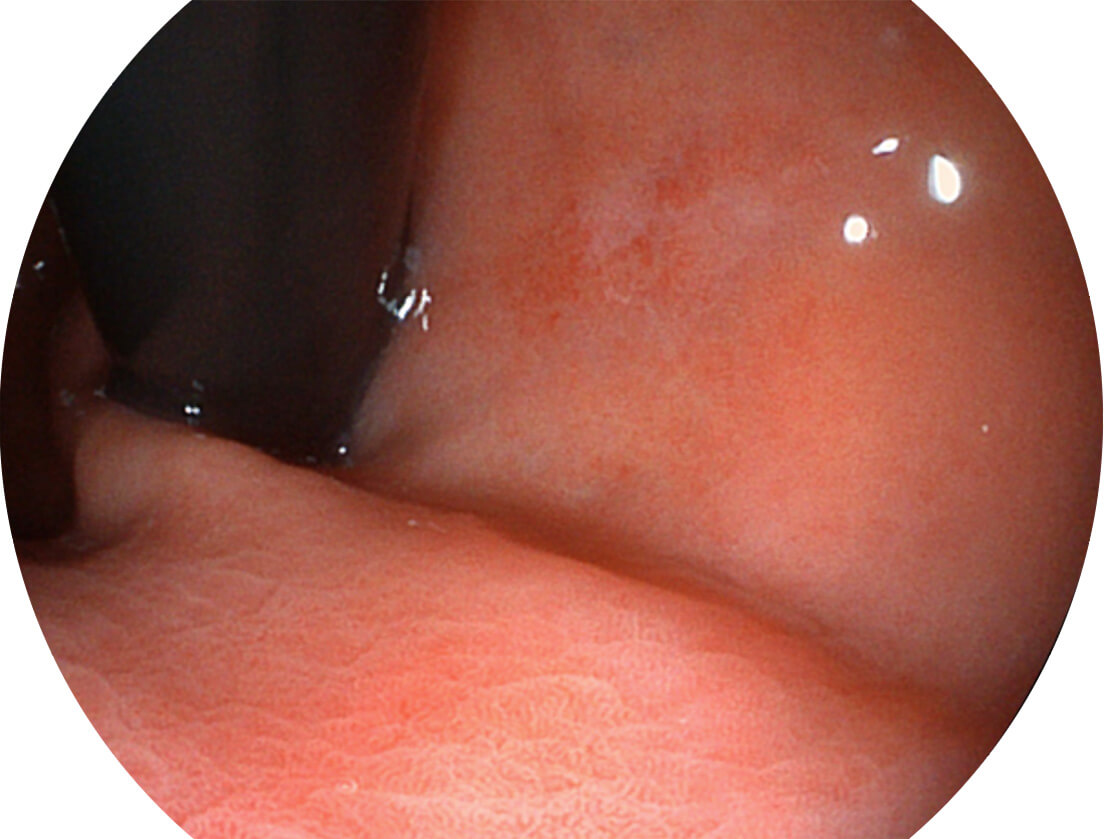

Versatile Intelligent Staining Technology, VIST

强调浅层黏膜结构的同时,保证照明亮度和提升浅层微血管与中层血管颜色对比度,病变边界更清晰。

白光图像

VIST图像

采用光路合束技术,光谱自由度高,实现了更丰富的照明模式,染色模式SFI及VIST,从远景到近景,助力消化道早期疾病诊断。